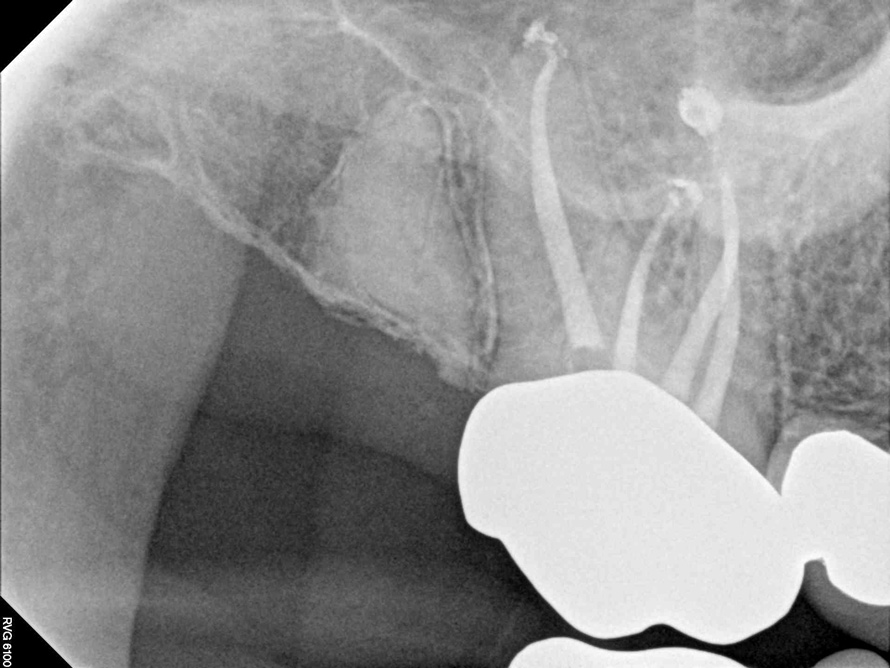

Fig 9. It is clinically acceptable to have results with the sealer puff (Figure 9) and without (Figure 10).

Figure 9

Fig 10. It is clinically acceptable to have results with the sealer puff (Figure 9) and without (Figure 10).

Figure 10